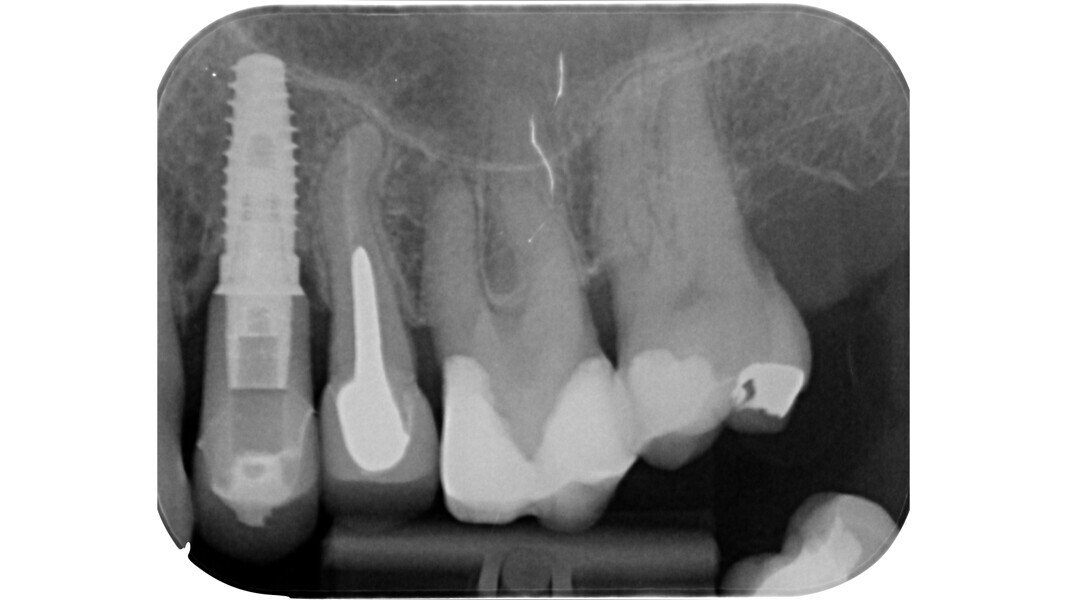

L’étape suivante est la phase de localisation et celle-ci peut s’avérer très difficile, surtout dans les dents calcifiées. Dans ce cas, le praticien doit laisser de côté les instruments rotatifs diamantés et recourir à divers dispositifs spéciaux.

Parmi ces lois, certaines revêtent une importance clinique fondamentale. Par exemple, dans des conditions plus difficiles, telles que dans le cas d’une préparation dentaire prothétique, où les points de repère classiques sont perdus, la connaissance des trois premières lois nous permet de tracer une cavité d’accès qui suit le contour de la dent, et de repérer les orifices à l’intérieur de cette zone. D’un point de vue embryogénétique, la couronne dentaire est la projection du développement du tissu pulpaire.

Le principe du diamant fait référence à l’utilisation d’un certain type de fraise diamantée pour la phase de pénétration, en particulier dans les molaires supérieures et inférieures, ainsi que dans les prémolaires supérieures biradiculées. Deutsch8–9 associe des mesures morphologiques à la relation entre la surface occlusale, la hauteur, la position du plafond et du plancher de la cavité dans les dents pluriradiculées. Dans ces éléments, le plafond de la cavité pulpaire est situé au niveau de la JAC.